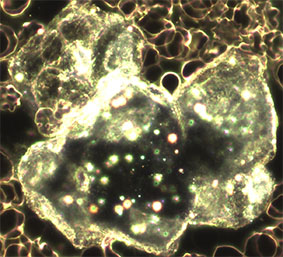

Aspergillus mit Schwermetall-Belastung